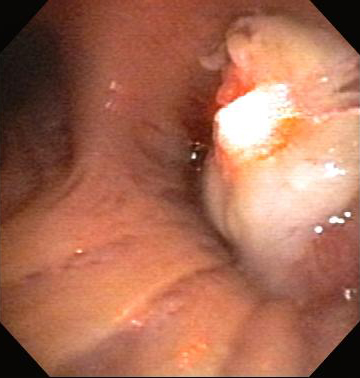

Nd:YAG is a non-contact or contact technique in which energy from an Nd:YAG laser is applied to the airway tissue for the relief of malignant and non-malignant CAO. [Figure caption and citation for the preceding image starts]: Central airway obstruction: malignant obstruction of the right mainstemFrom the collections of Jose Fernando Santacruz MD, FCCP, DAABIP and Erik Folch MD, MSc; used with permission [Citation ends].

[Figure caption and citation for the preceding image starts]: Bronchoscopic therapy for central airway obstruction of the right mainstem: laser photoresectionFrom the collections of Jose Fernando Santacruz MD, FCCP, DAABIP and Erik Folch MD, MSc; used with permission [Citation ends].